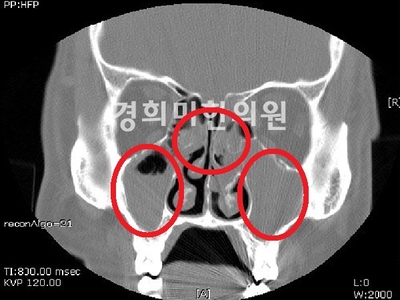

부비강염 CT이미지